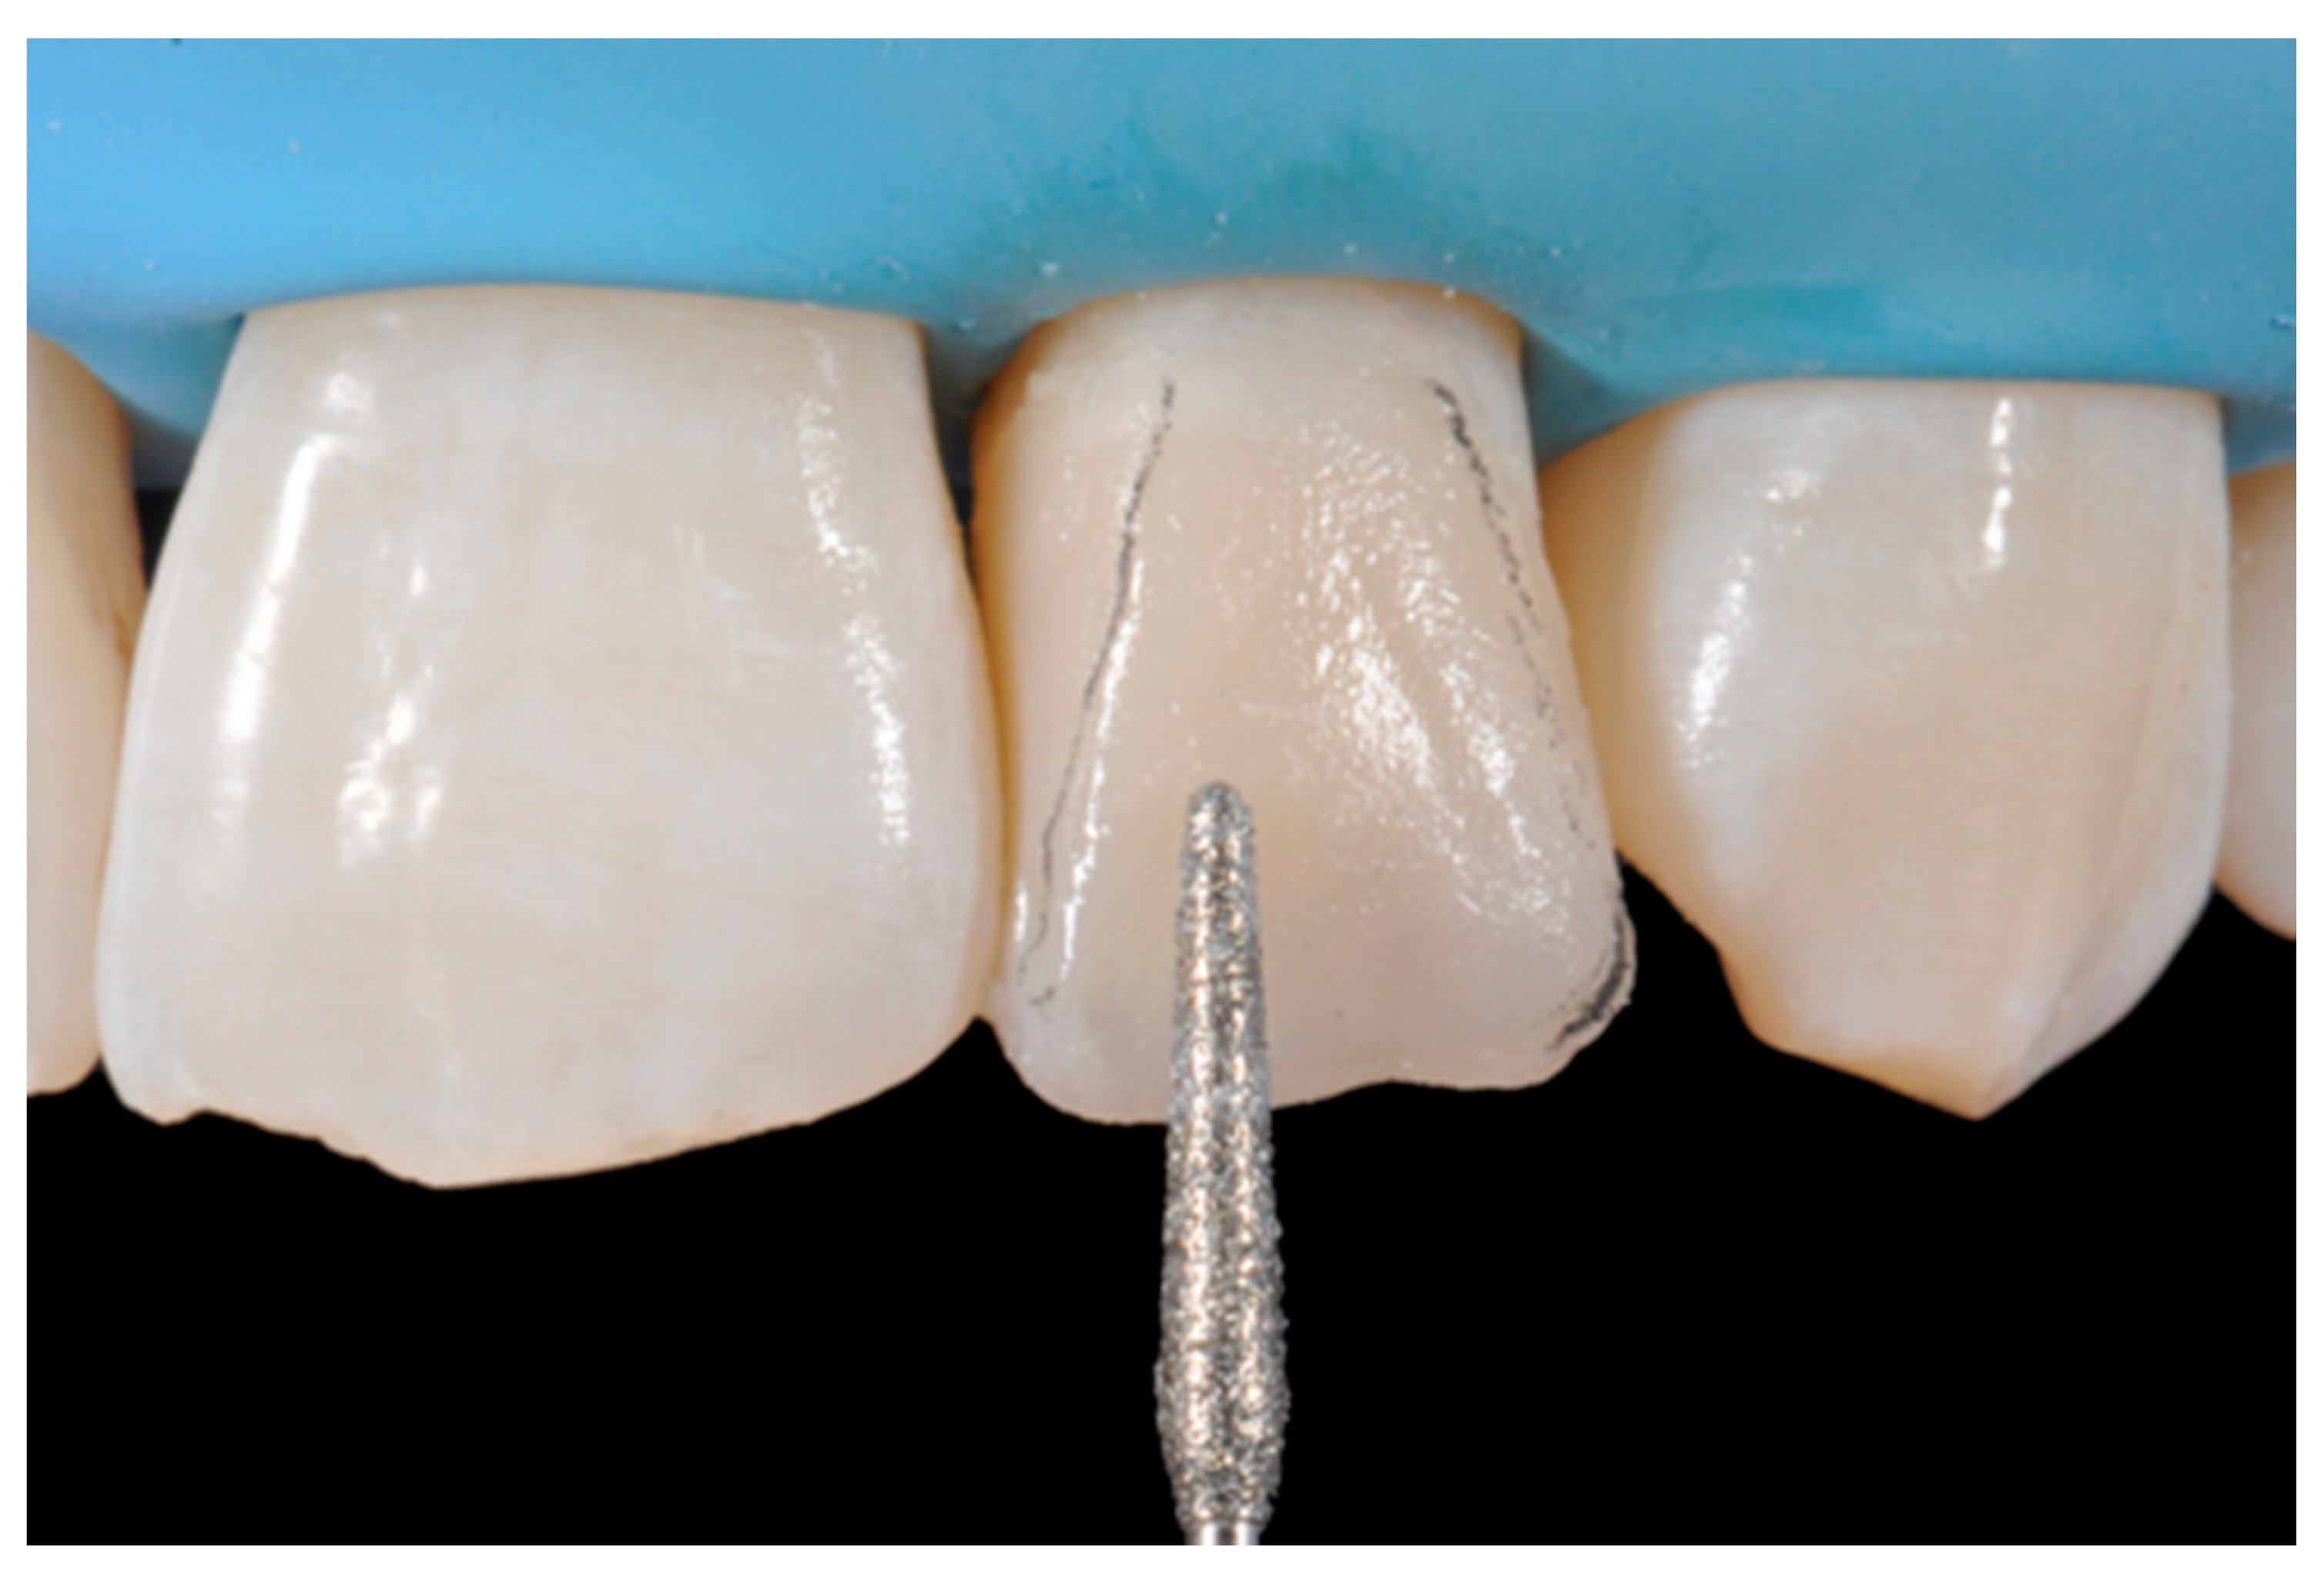

- Burs (WL 268 014 Horico, Berlin, Germany);

- Discs (Sof-Lex, 3M ESPE, St. Paul, MN, USA) (Figure 7);

Figure 7. External frame profile is modified with abrasive discs. Reprinted from Restauri diretti nei settori anteriori, G. Paolone, S. Scolavino, © 2021, with permission from Quintessence Publishing Italy. - Abrasive stripes (Sof-Lex, 3M ESPE, St. Paul, MN, USA);

The internal ones can be reduced with diamond burs (WL 268 014 Horico, Berlin, Germany) (Figure 8).

Figure 8.

Excessive thickness of interproximal walls is reduced with a low-speed diamond bur. Reprinted from Restauri diretti nei settori anteriori, G. Paolone, S. Scolavino, © 2021, with permission from Quintessence Publishing Italy.